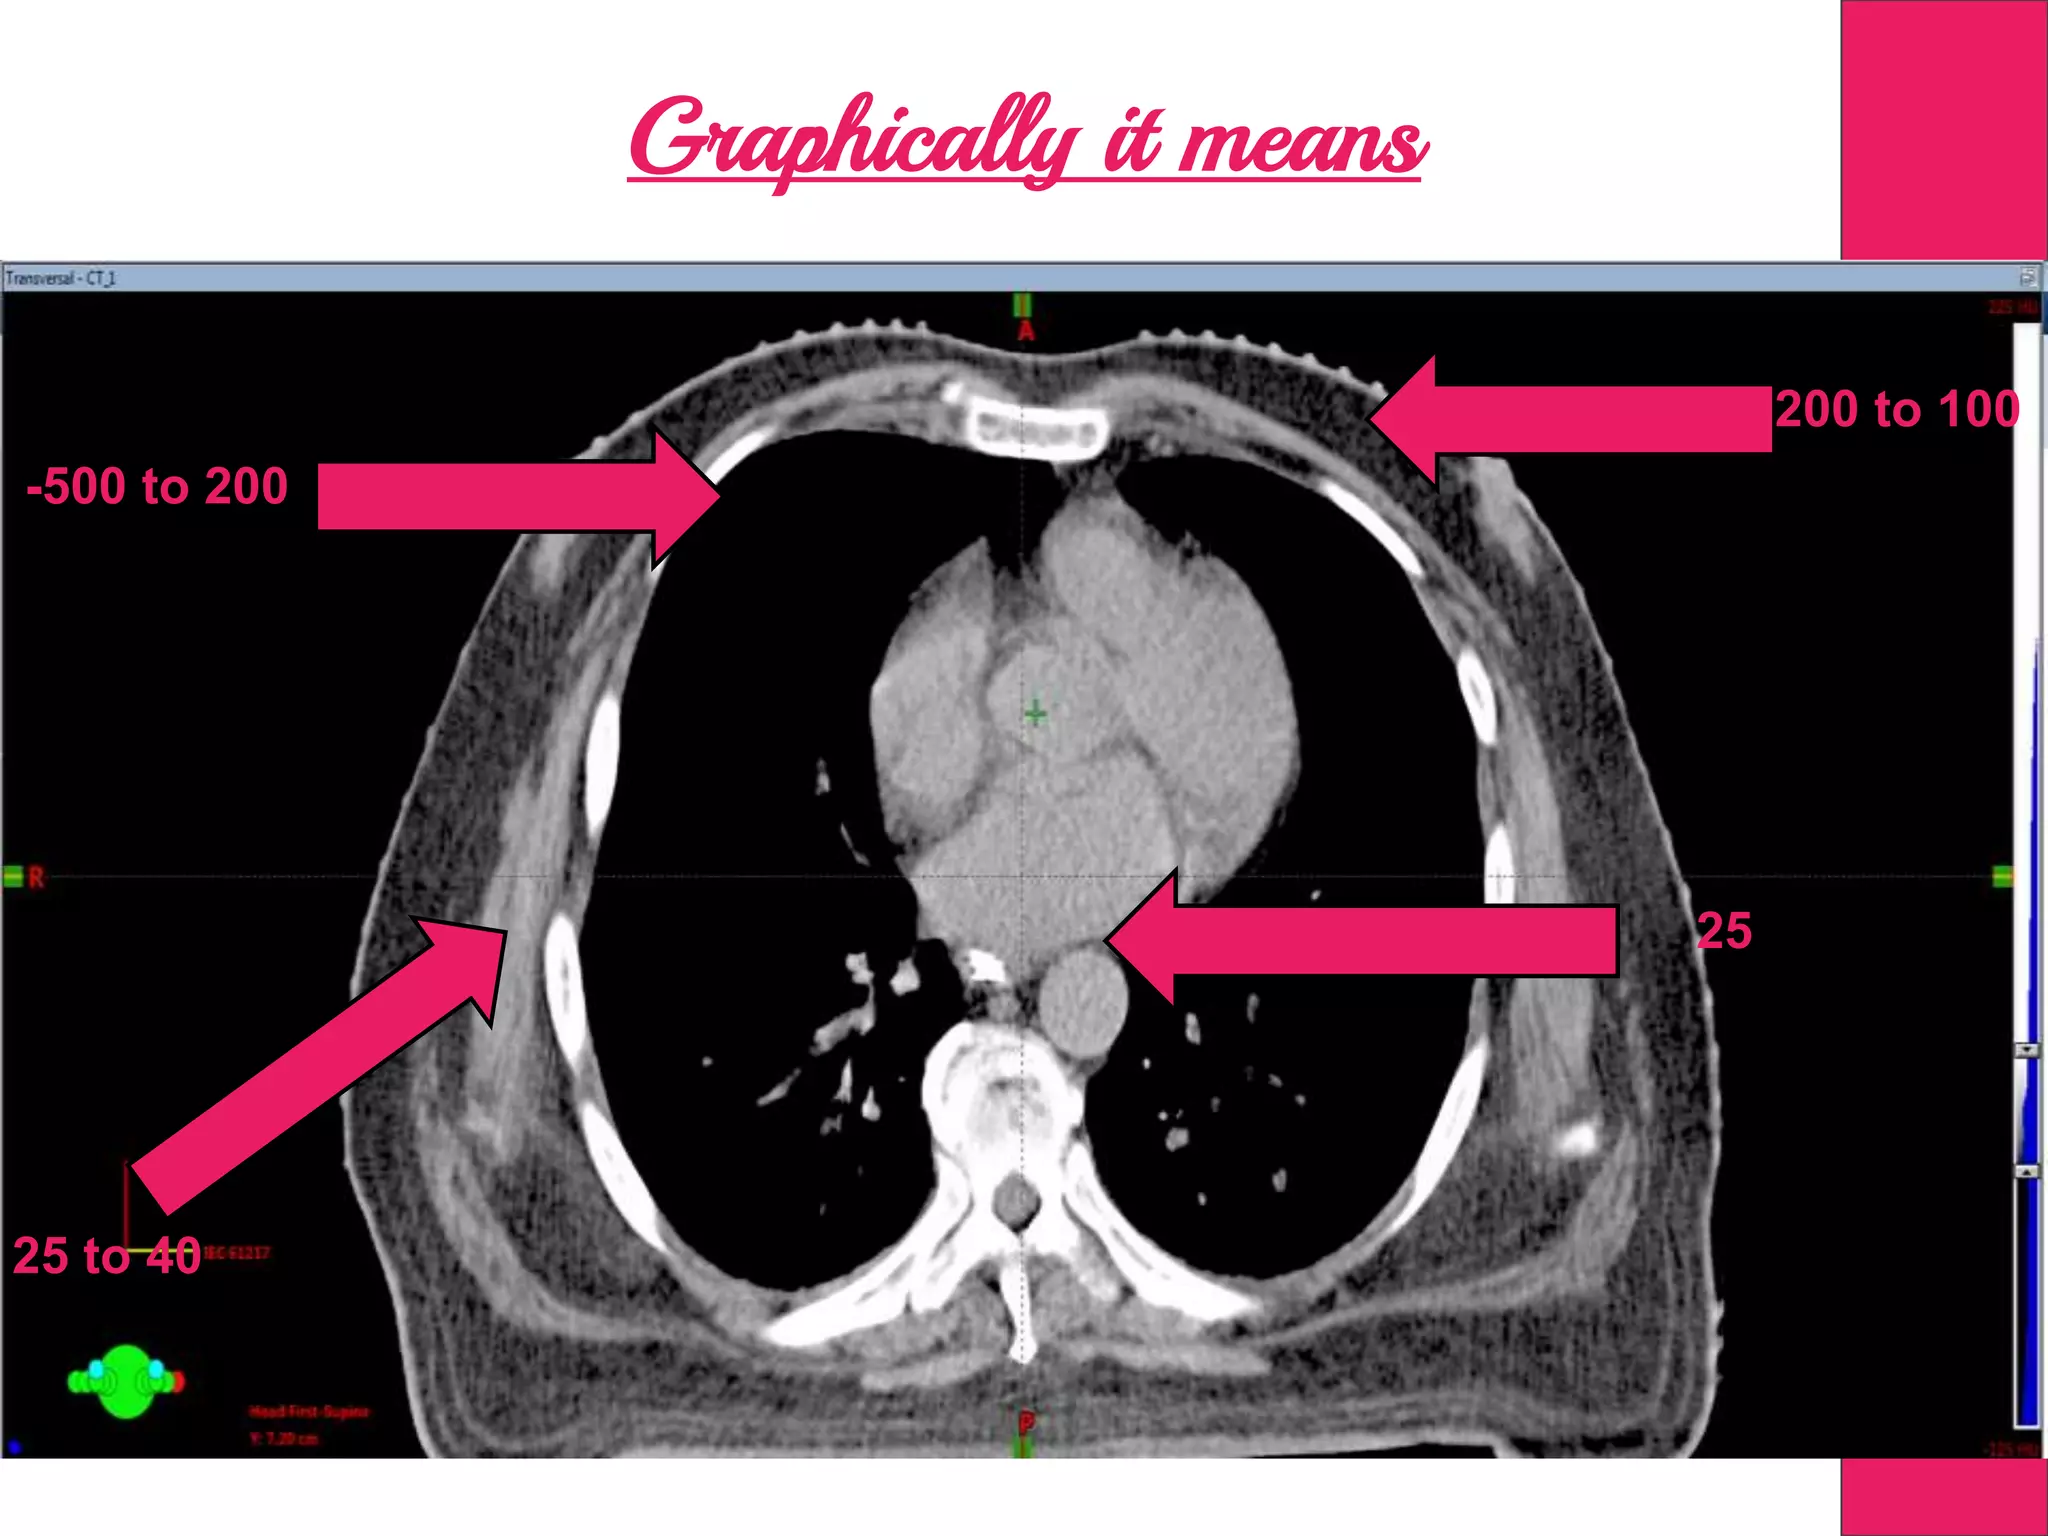

Graphically it means

-500 to 200

-200 to 100

25 to 40

25

HU value equates the Electron Density of the Tissue

Graphically it means -500to 200 -200 to 100 25 to 40 25

HU value equatesthe Electron Density of the Tissue